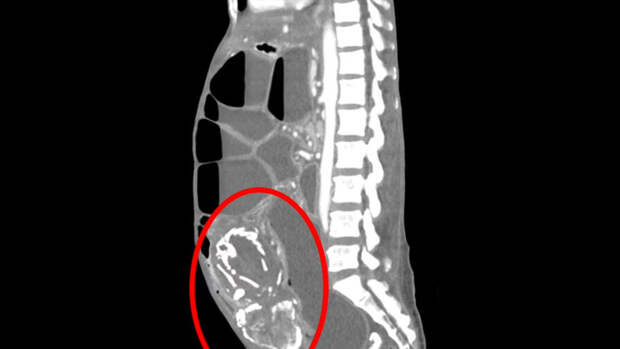

Сканирование обнаружило в теле 50-летней женщины литопедиона —"каменного ребенка", представляющего собой кальцифицированный плод.Это редкое явление было зарегистрировано менее 300 раз, впервые — во Франции в 1582 году. Плод может кальцифицироваться, умерев при внематочной беременности. В некоторых случаях женщины вынашивают плод десятилетиями, не зная об этом.